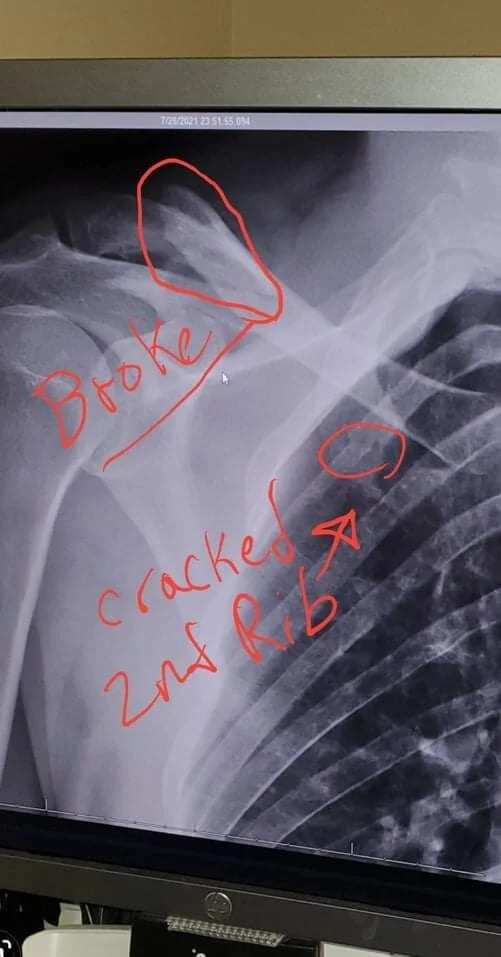

The result was a broken collarbone, a cracked rib, a small hairline fracture in my hip and a minor concussion. Had I not been wearing a helmet it is quite easy to imagine that I would not be here telling this story right now. Anyway I just thought it was worth a share. I Hope that it may teach some of you that even if you're an excellent Rider and doing everything right in a split second things can change! Sometimes something as simple as a helmet can make all the difference.